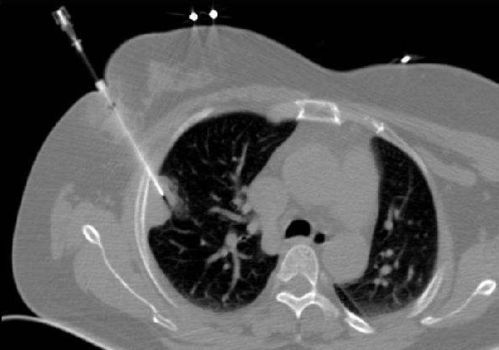

最主要的并發(fā)癥為肺內(nèi)出血及氣胸,最好在CT引導(dǎo)下進(jìn)行以提高準(zhǔn)確性,由富有操作經(jīng)驗(yàn)的醫(yī)師來(lái)做,可提高成功率及減少并發(fā)癥。手術(shù)中對(duì)某些特殊麻醉劑要按使用說(shuō)明進(jìn)行(有些要做過(guò)敏試驗(yàn))。

只是穿刺適用于外周性包塊,離胸壁較近的。最大的副反應(yīng)是氣胸,發(fā)生率較低,且容易處理。